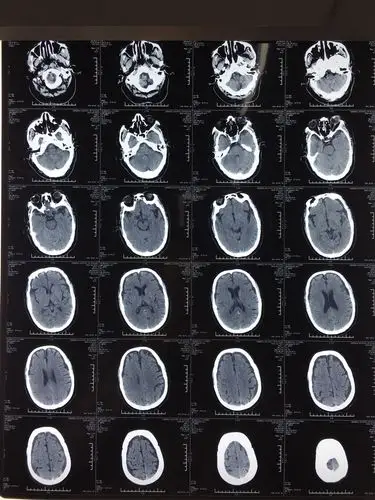

两种常见脑萎缩ct表现